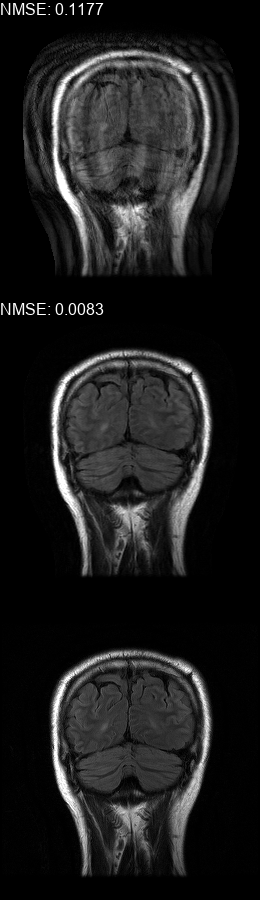

Fig. 5 contains four scan reconstructions from two patient cases. In both cases, the patient was requested to move at a certain time. In order to provide a ground truth for this scenario, another scan was performed using the same protocol for each patient, where the patient was required to hold still. The motion timing information for this case was obtained using the method described in [2] as it requires no additional hardware or changes to the scan protocol. We compare the reconstruction error using the SSIM [17] and the Visual Information Fidelity (VIF) [16] metrics, since a pixelwise comparison is not viable in this case.

Figure 5: Examples of real motion corrupted images together with their motion corrected counterparts. The bottom row shows a corresponding slice from a motion-free acquisition of the same subject. These motion-free images were acquired using an additional scan. The images on the top row are motion-corrupted. Images on the middle row were corrected using our method. (a,b) motion was was detected at t1=96subscript𝑡196t_{1}\!=\!96, (c,d) the motion was detected at t1=112subscript𝑡1112t_{1}\!=\!112. All scans were acquired using 𝒮260subscript𝒮260\mathcal{FS}_{260} presented in Fig. 1b.